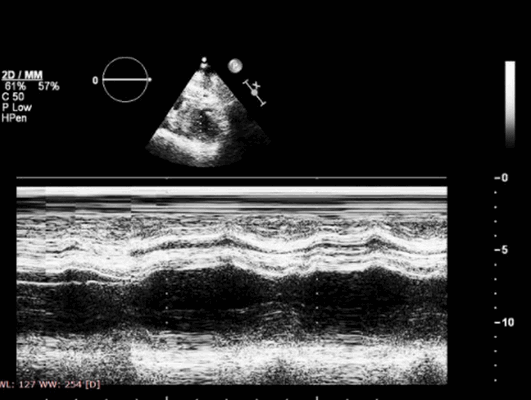

Аортальный клапан и левое предсердие на эхокардиограмме в М-режиме

Эхо-сигналы, регистрируемые от корня аорты в М-режиме, должны быть параллельными, перемещаясь кпереди в систоле и кзади в диастоле. Когда датчик наклонен немного медиально, можно визуализировать два из трех полулунных выступов. Правая коронарная створка будет показана спереди, а некоронарная створка - сзади. При осмотре левая коронарная створка будет находиться по средней линии между двумя другими створками. Начало систолы приводит к тому, что створки полностью раскрываются до корня аорты. Интенсивный поток крови через это отверстие вызывает мелкое трепетание створок во время систолы. По мере того, как давление в желудочке спадает, створки начинают сдвигаться в закрытое положение, пока они полностью не закроются в диастоле.

Камера позади корня аорты в М-режиме на эхокардиографии будет левым предсердием, которое можно узнать по неподвижной задней стенке. При движении от митрального аппарата кнутри и вверх стенка левого желудочка сливается с предсердно-желудочковой бороздой и, наконец, со стенкой левого предсердия. Таким образом, развертка в М-режиме в норме демонстрирует хорошую сократимость левого желудочка с движением передней стенки в систоле в атриовентрикулярную область, где задняя стенка начинает сокращаться также в систоле, затем двигается в направлении левого предсердия, где движение отсутствует.

Другие структуры, расположенные кзади от полости левого предсердия, которые могут привести к путанице при идентификации стенки левого предсердия, — это ушко левого предсердия и нисходящая аорта. Ушко левого предсердия может выступать кзади от стенки левого предсердия, если имеется сильное увеличение полости левого предсердия (особенно это наблюдается у пациентов с тяжелым поражением митрального клапана). Оценка при двухмерной эхокардиографии с датчиком в апикальной четырехкамерной позиции выявляет ушко левого предсердия как отдельную структуру. Нисходящую аорту также можно распознать как параллельную пульсирующую трубчатую структуру, расположенную кзади от полости левого предсердия. Аорта не является продолжением стенки левого желудочка, как и стенка левого предсердия. Таким образом, врач УЗИ должен уметь различать эту структуру на эхокардиографии как нормальную анатомию сердца.